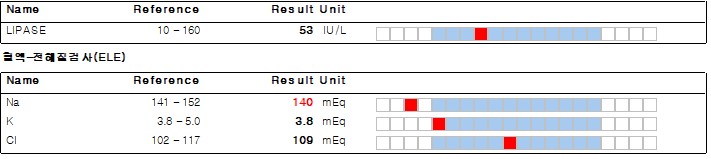

몽*은 설사와 식욕 부진으로 강서구 까치산역 세인트동물병원에 내원하였습니다.기초적인 문진 후 혈액검사를 실시했습니다.

혈액 검사에서는 염증 수치가 상승한 것 이외에는 별다른 소견이 없었습니다.